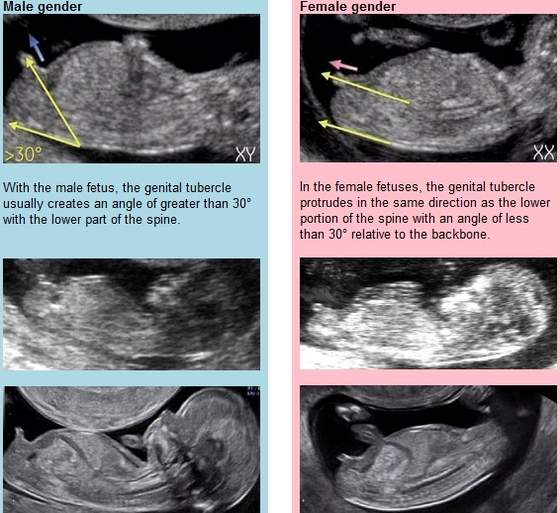

12 pazdziernika, czyli juz w 18 tygodniuco do płci to mam bardzo fajny obrazek

Zobacz załącznik 708507